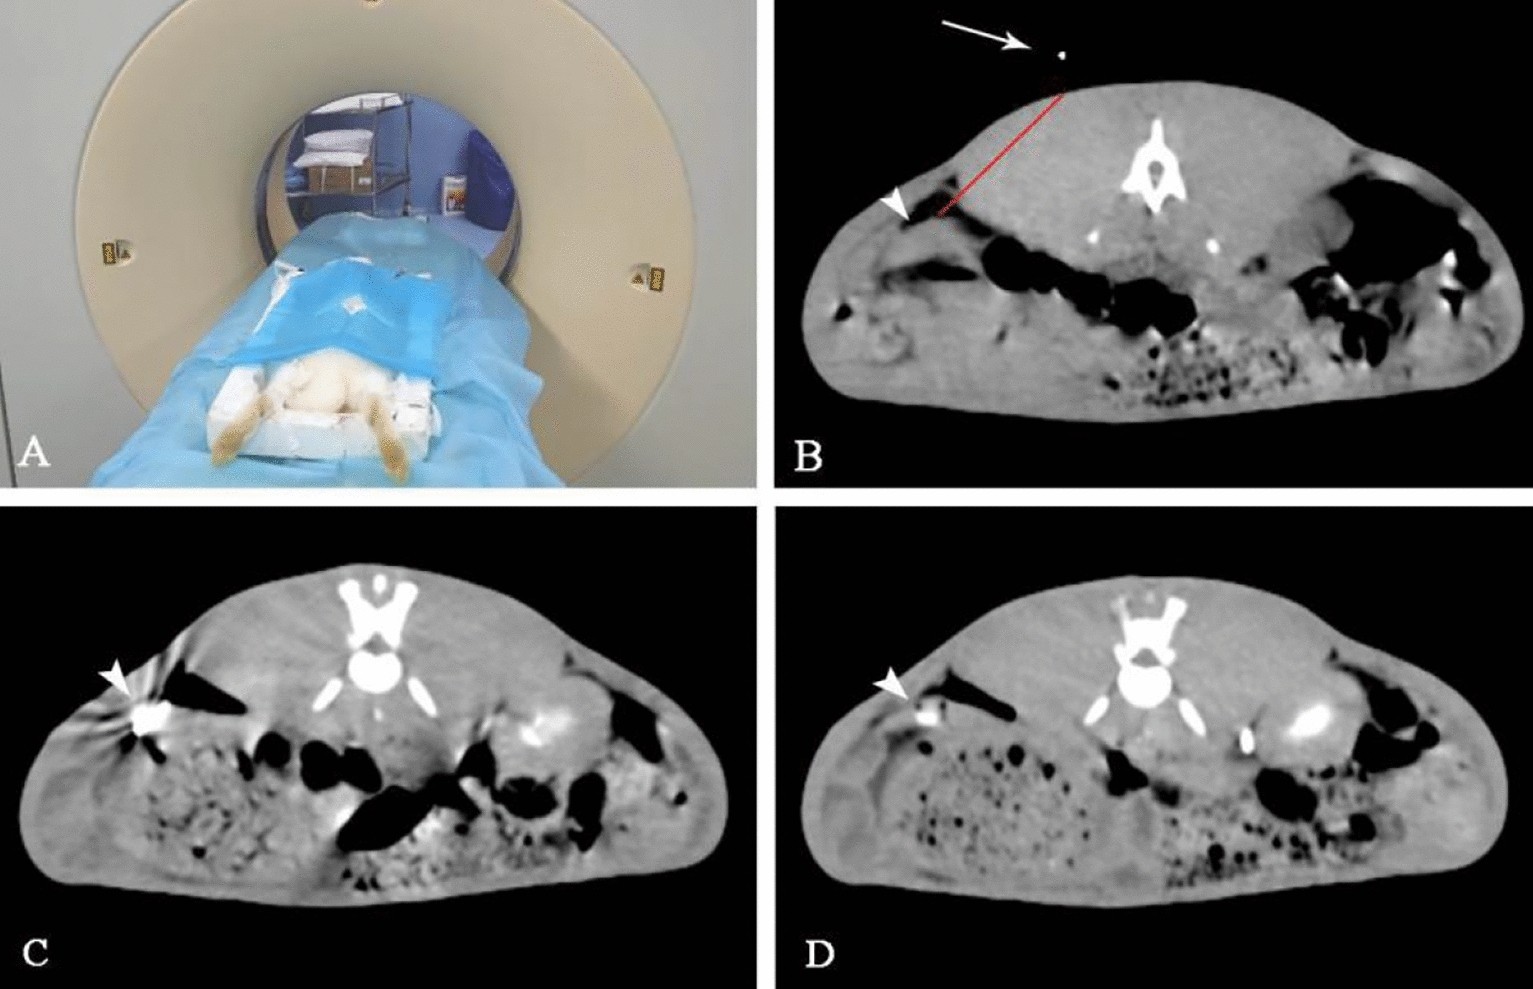

Figure 2

CT-guided percutaneous splenic implantation. The rabbits were fixed on the CT scanning table in a prone position (A); A self-made metal positioner (arrow) was used for positioning, the puncture path was determined (red line) (B), spleen (arrowhead); a 22G coaxial puncture needle (arrowhead) was used to puncture the rabbit spleen (C); The needle path was blocked with a gelatin sponge (arrowhead) (D).